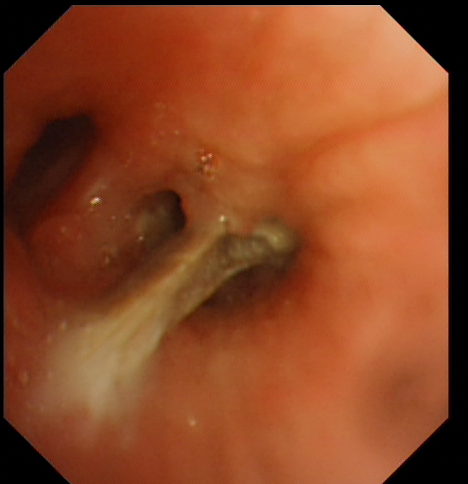

患者玉某,女,58岁,南宁扶绥人,1年前开始莫名频繁咳嗽,甚至后来出现了气喘,晚上也睡不安,吃药、输液都不见效果。2012年来我院呼吸内科住院,经过我科医生详细体检,发现患者右侧肺部有明显的喘鸣音。追问病史,似曾有异物呛入史,仔细查看胸部CT片发现,右肺下叶支气管腔内有高密度影,初步诊断:气管异物?在科室谭玉萍主任的指导下,潘玲主治医师对周某进行了电子支气管镜检查,发现在右下肺基底段支气管内有一淡黄色的骨性异物,已嵌入周围气管组织。通过呼吸内科工作人员密切配合,历时20分钟,终于将横在右下肺基底段支气管内的异物完整取出。异物取出后,患者咳嗽随之解除。住院四天,玉某康复出院。

据玉某事后回忆,1年前她有一次在吃鱼时好像感觉有一个鱼骨卡了一下喉咙,至于异物如何跑到气管里则不得而知。对此,谭玉萍主任表示,异物一旦进入气管、支气管,自然咳出的机会仅有2%左右。异物留在气道中很容易引发阻塞性肺炎,甚至引起大咯血,可危及生命。群众吃饭吃鱼时应细嚼慢咽,避免边吃边聊,更不能打逗,以免食物呛入气管。一些长期咳嗽却查不出原因的患者应及早就医,在医生指导下进行支气管镜等检查,可及时发现病因。